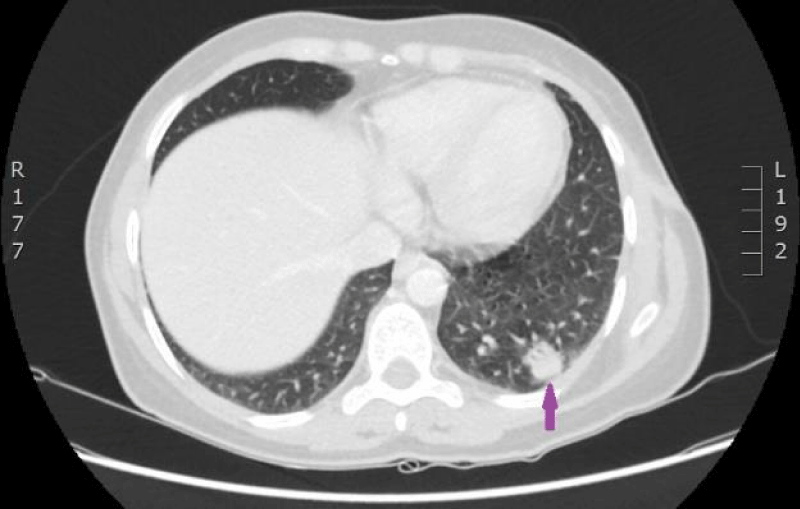

On 29th of December 2016 the woman was hospitalized to P.Stradins CUH for performing control CT of lungs and abdomen to decide whether to continue the third line of chemotherapy. Physical examinations revealed slightly harder supraclavicular lymph nodes bilaterally, however their size was normal. On 29th December 2016, computed tomography of the lungs and the abdomen was performed which showed progressive lymphangitis, new subpleural metastases (Figures 20-22) why the third line of chemotherapy was discontinued. The tumor sample was tested for ROS1 mutation using NGS methodology. Examination found SLC34A2-ROS1 fusion and excluded mutations of EGF, KRAS, ALK, BRAF, MET, RET, ERBB2 genes.

Figure 20: CT scan of the lungs on 29th­ of December 2016. Lymphangitis has progressed in the upper lobe of the right lung; new subpleural metastases are seen. (Images from Diagnostic Radiology Institute of P. Stradins CUH).

Figure 21: CT scan of the lungs on 29th­ of December 2016. Lymphangitis has progressed in the upper lobe of the right lung; new subpleural metastases are seen. (Images from Diagnostic Radiology Institute of P. Stradins CUH).

Figure 22: CT scan of the lungs on 29th­ of December 2016. Lymphangitis has progressed in the upper lobe of the right lung; new subpleural metastases are seen. (Images from Diagnostic Radiology Institute of P. Stradins CUH).